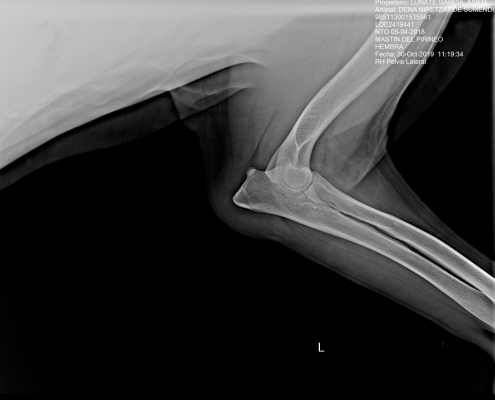

DENA NIRETZAT DE SUMENDI